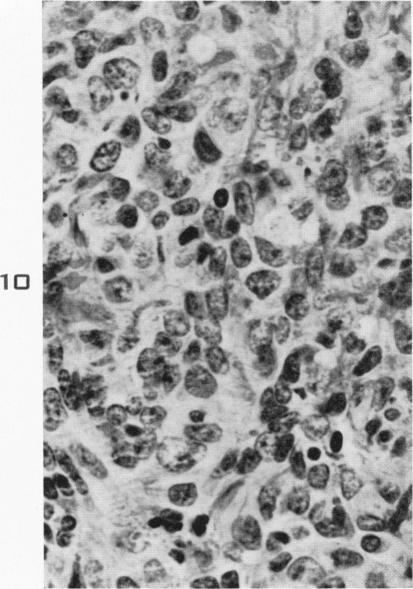

Muco-epidermoid tumors of the bronchus arising from surface epithelium.

Am J Pathol. 1958 Jul-Aug;34(4):671-83.